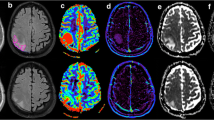

The MR imaging was performed with a 3-T Signa system (GE Medical Systems, Milwaukee, Wis., USA). A standard quadrature head coil (GE Medical Systems) was used for the all patients. Each MR examination included precontrast transverse T2- and T1-weighted spin-echo imaging followed by diffusion-weighted images. The perfusion-weighted imaging and MR spectroscopy were performed after contrast material administration. In each study T2-weighted images were acquired using a spin echo sequence with a TR/TE of 4000/100, a slice thickness of 3 mm and field of view of 240×180. Precontrast T1-weighted images were then acquired with a slice thickness of 3 mm and a TR/TE of 800/9 (Fig. 1). Postcontrast axial images were obtained after perfusion-weighted images. Subsequent diffusion-weighted and spectroscopic imaging were also performed.

Localizing image from axial T1-weighted images in a 46-year-old man with pathologically confirmed glioblastoma multiforme. a Localizing image from postcontrast axial T1-weighted MR demonstrates the voxel position at intratumoral region (voxel 1). There is elevation in Cho/Cr to 1.98. The voxel position at peritumoral region with corresponding spectrum (1000/144) demonstrates elevated Cho/Cr, 1.84, in keeping with tumoral infiltration in the peritumoral region (voxel 2). b There is elevation in peritumoral rCBV (voxel 2) to 122%, compared with intratumoral rCBV (voxel 1) and the contralateral normal white matter used as a control (voxel 3). The measured signal vs. time curves corresponding to the tumor and peritumoral voxel positions. The curves 1 and 2, corresponding to the voxels at the tumor and peritumoral regions, reveal increased enhancement of the signal after the bolus arrival

The ADC values measured in the tumors and the surrounding edema are shown in Table 1. The ADC values in tumor regions (high-grade gliomas 1.04±0.42, metastases 1.87±0.73, P<0.005) and ADC in peritumoral regions (high-grade gliomas 2.01±0.37, metastases 2.41±0.33, P<0.05) were calculated. High ADC values were identified in cystic and necrotic areas. In the peritumoral edema of metastases and high-grade gliomas the ADC were higher than those in contrast enhancing tumor. We found the mean ADC values at contrast-enhancing areas and peritumoral edema of metastases to be significantly higher than those in high-grade gliomas. Table 1 also summarizes the results of the rCBV values. Our main findings reveal statistically significant differences in the rCBV in peritumoral region (high-grade gliomas 2.33±1.61, metastases 0.84±0.33, P<0.005). The Cho/Cr ratio in peritumoral region in high-grade gliomas and metastases was 1.30±0.45 and 0.29±0.51 respectively (P<0.001). The intratumoral rCBV, Cho/Cr, NAA/Cr, and peritumoral NAA/Cr ratios in high-grade gliomas did not differ statistically from those seen with metastases (Table 1). Within the enhancing portion of the cerebral metastases lipids (at 0.9 ppm) and lactate (at 1.35 ppm) were detected (Fig. 2a; see also Fig. 3).

Localizing image from postcontrast axial T1-weighted MR in a 74-year-old woman with a metastatic tumor from bronchogenic carcinoma. a The voxels of interest on the three positions: 1 Intratumoral spectrum (1000/144), with the voxel in the tumor, demonstrates Cho/Cr elevation to 3.41 and NAA/Cr reduction. The spectrum of this metastatic tumor could not be differentiated from that of the high-grade glioma. 2 Peritumoral spectrum (1000/144) demonstrates no evidence of tumoral infiltration in peritumoral region. There is a diminution of Cho/Cr ratio to 1.14. 3 Spectrum (1000/144) in the contralateral normal white matter is included to ensure that the abnormal spectra are of diagnostic quality. b A left occipital lesion at color map (left). Peritumoral rCBV (voxel 2) is reduced to 35%, compared with voxel 3, in the contralateral normal white matter used as a control. The measured signal vs. time curves correspond to the three voxel positions (right). Curve 2 at the peritumoral region reveals nonsignificant enhancement of the signal after the bolus arrival